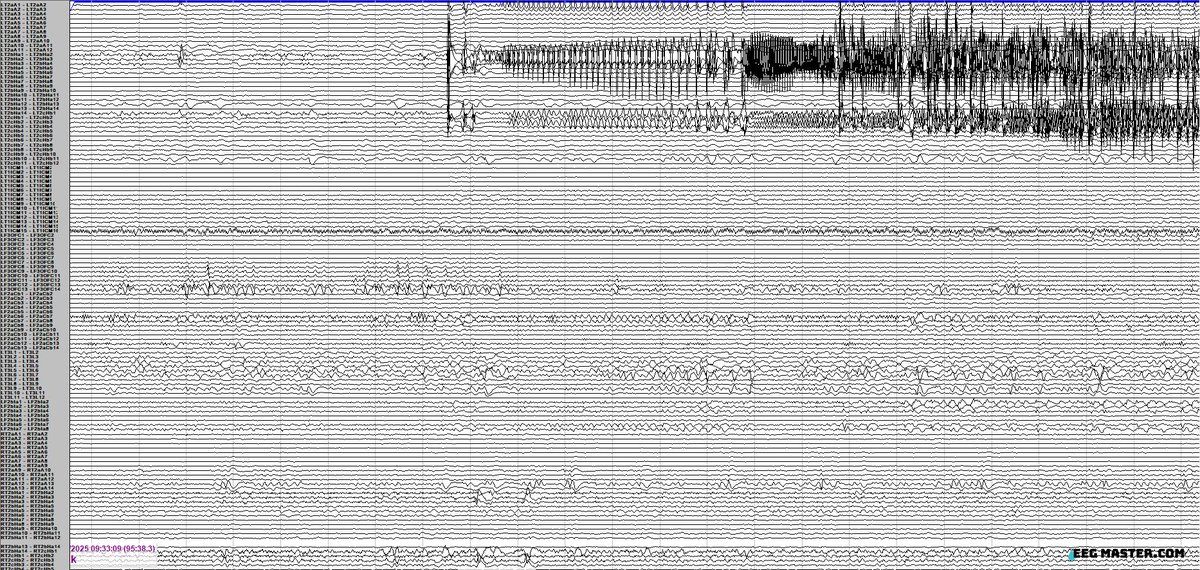

34 yo with seizures described as hot flashes -> staring, oral automatisms & right hand tonic-clonic movements. Using the sEEG provided (electrode labels per SENSA) localize his onset? Click on the link to see options, submit answer & view explanation.  eegmaster.com/eegmaster/quiz…